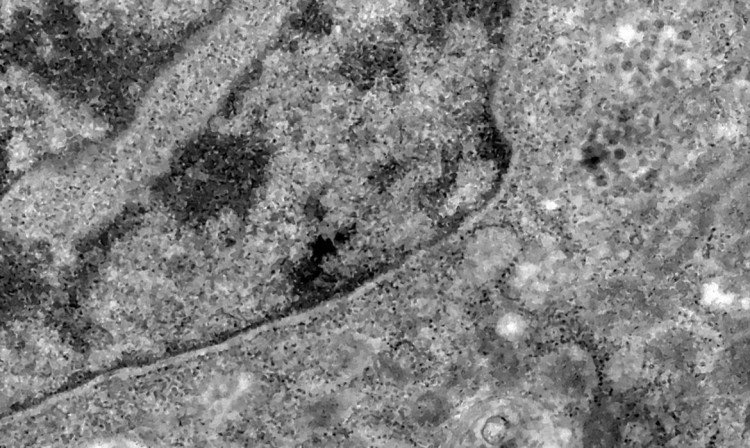

O surgimento de uma variante no novo coronavírus confirmado em regiões da África preocupa especialistas internacionais de saúde. Batizada de Ômicron - letra grega correspondente à letra “o” do alfabeto -, a cepa B.1.1.529 foi identificada em Botsuana, país vizinho à África do Sul, em meados de novembro. Segundo a Organização Mundial da Saúde (OMS), a variante pode se tornar responsável pela maior parte de novos registros de infecção pelo novo coronavírus em províncias sul-africanas.

Nos casos analisados, constatou-se que a variante é portadora de dezenas de mutações genéticas que podem afetar os índices de contágio e de letalidade. A OMS, entretanto, afirmou que ainda não há estudos suficientes para afirmar as propriedades da Ômicron, mas que já existem esforços científicos acelerados para estudar as amostras. Um time de cientistas de universidades da África do Sul está decodificando o genoma da Ômicron, juntamente com dezenas de outras variantes do novo coronavírus.

Tulio de Oliveira, diretor do Centro para Respostas e Inovações Epidêmicas da universidade de KwaZulu-Natal, afirmou em coletiva de imprensa que a variante Ômicron possui “uma constelação incomum de mutações”. A variante Delta, por exemplo, possuía duas mutações em relação à cepa original do novo coronavírus, enquanto a Ômicron possui cerca de 50 - 30 delas localizadas na proteína Spike, responsável por infectar células saudáveis, explicou o brasileiro.